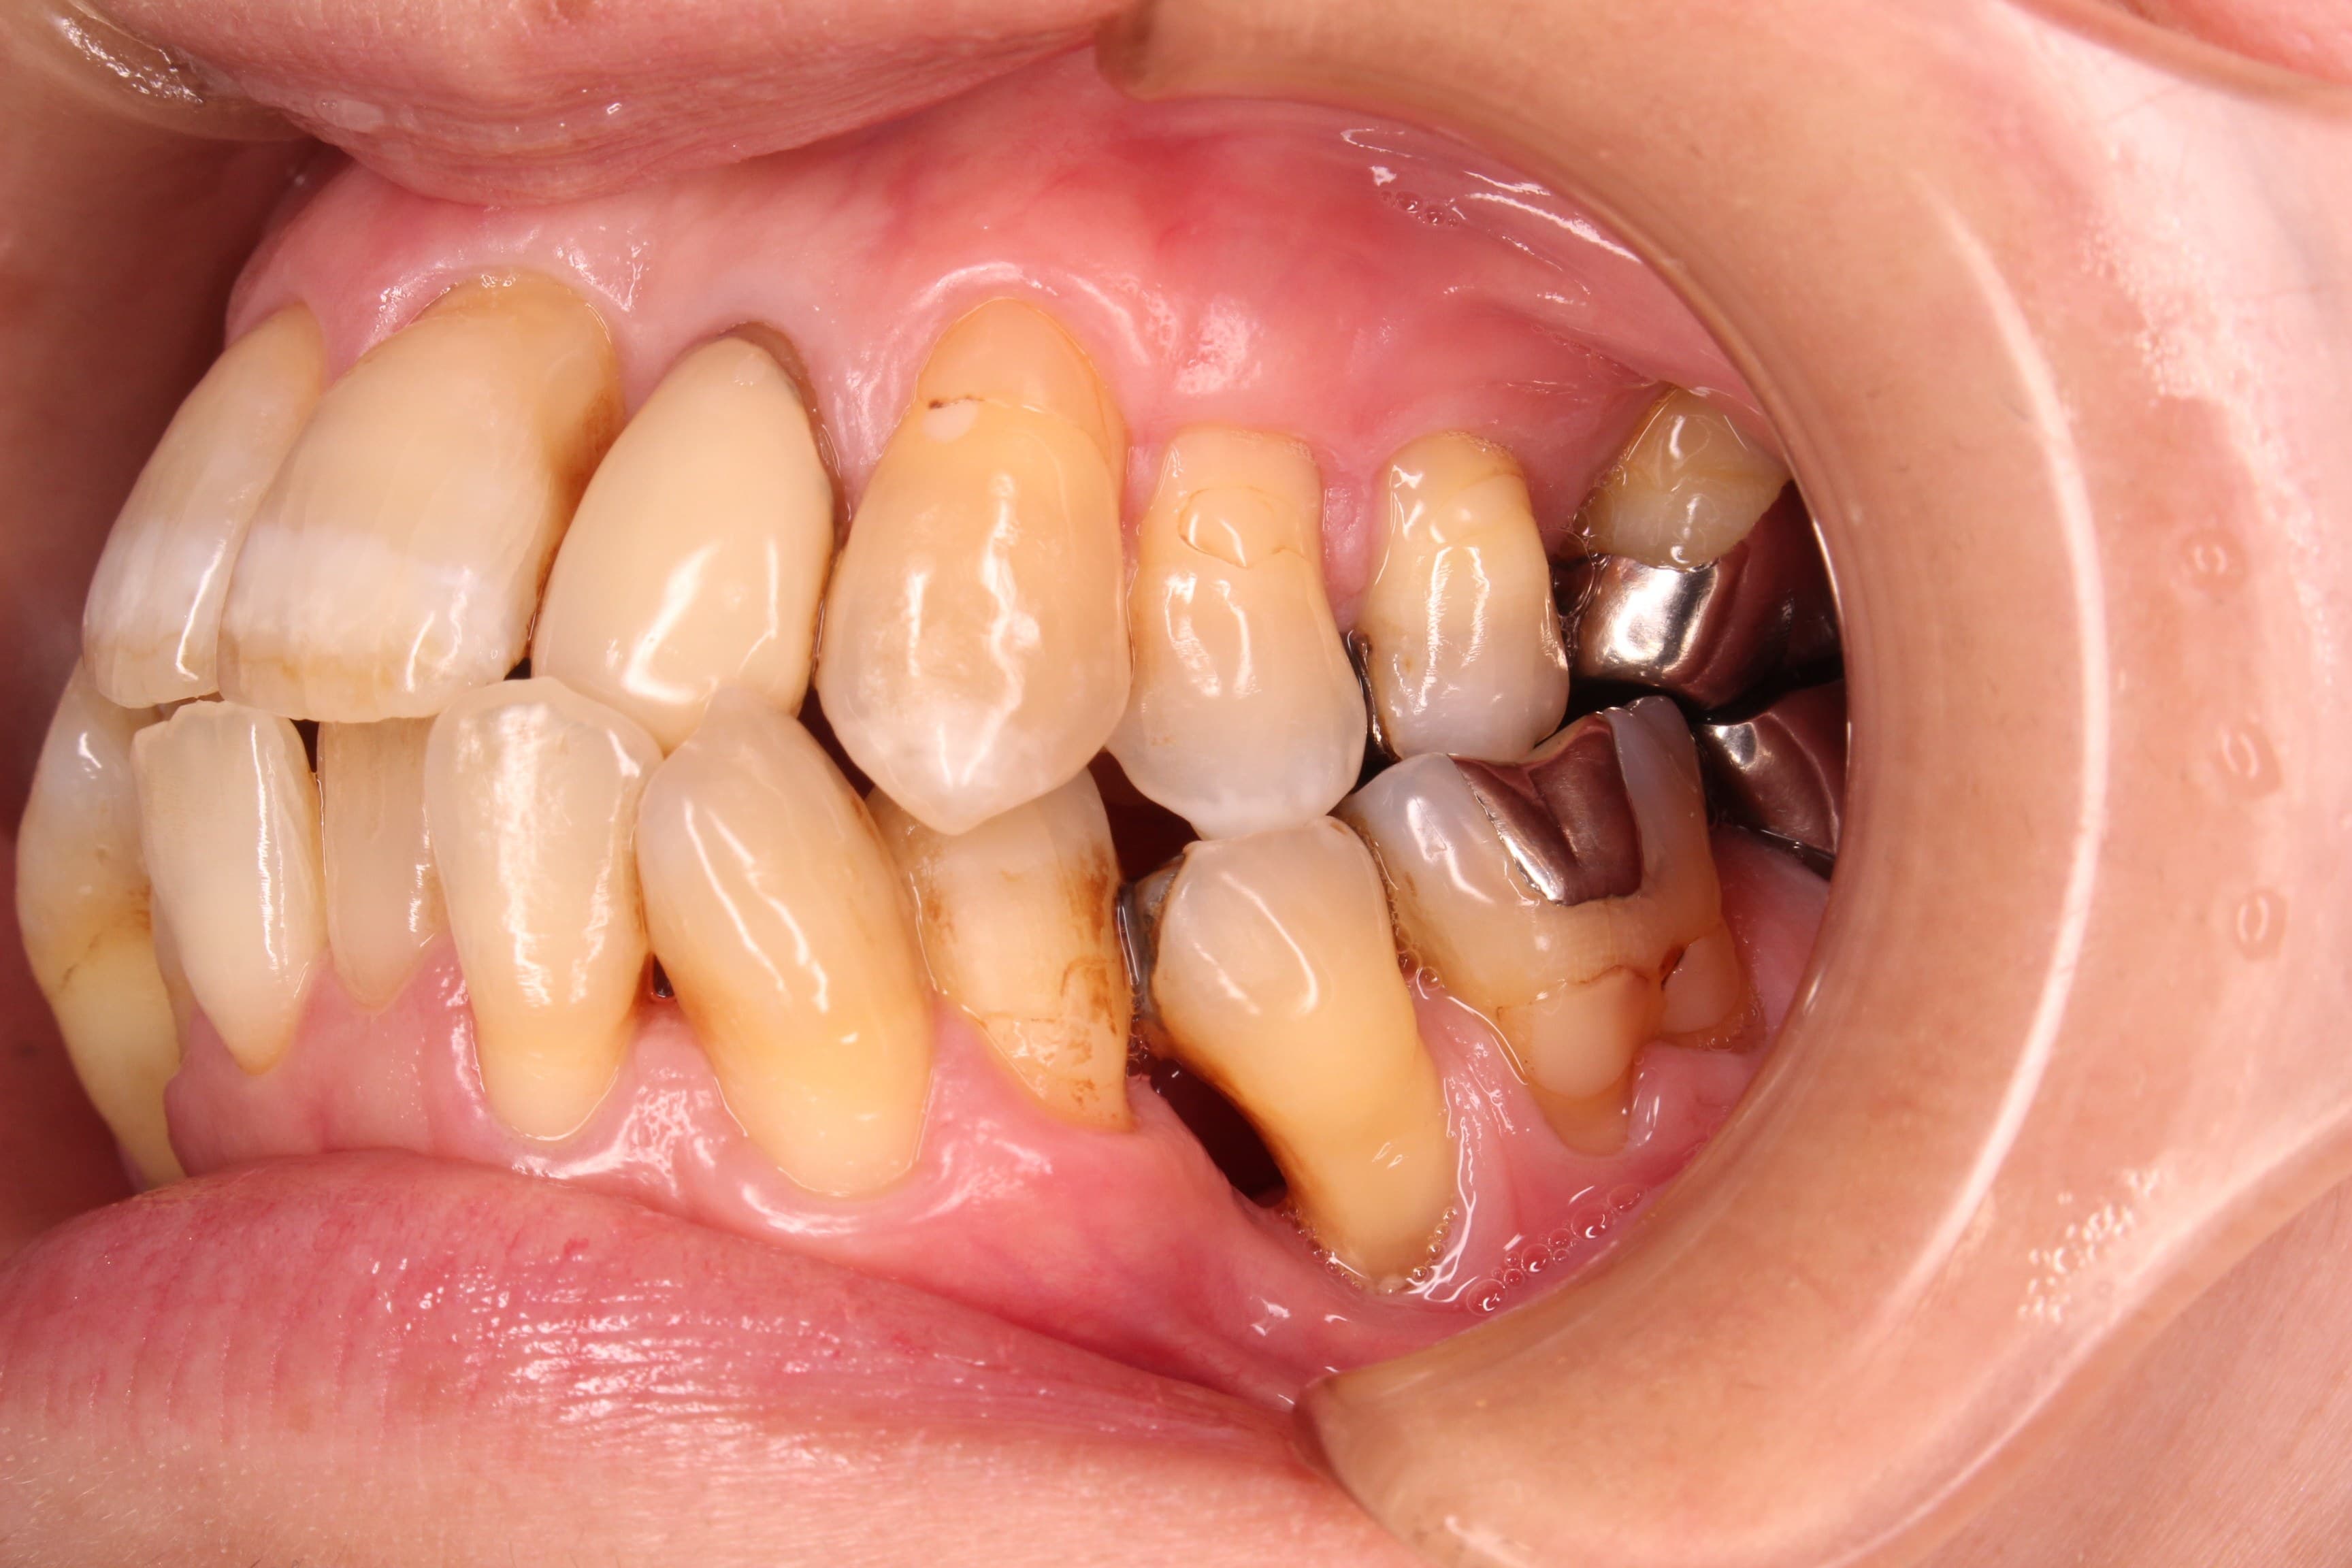

今回ご紹介する歯周専門治療のケースは、50代女性の方です。

20年前から歯周病が進まないように、2ヶ月に1度他院で定期健診を受けていました。

4~5年前から歯が動いている事に気付いており、そのまま元の歯科医院で定期健診を続けて経過観察をしていたそうです。

<治療前>

残念ですが、骨が大きく無くなっている所が数か所ありました。